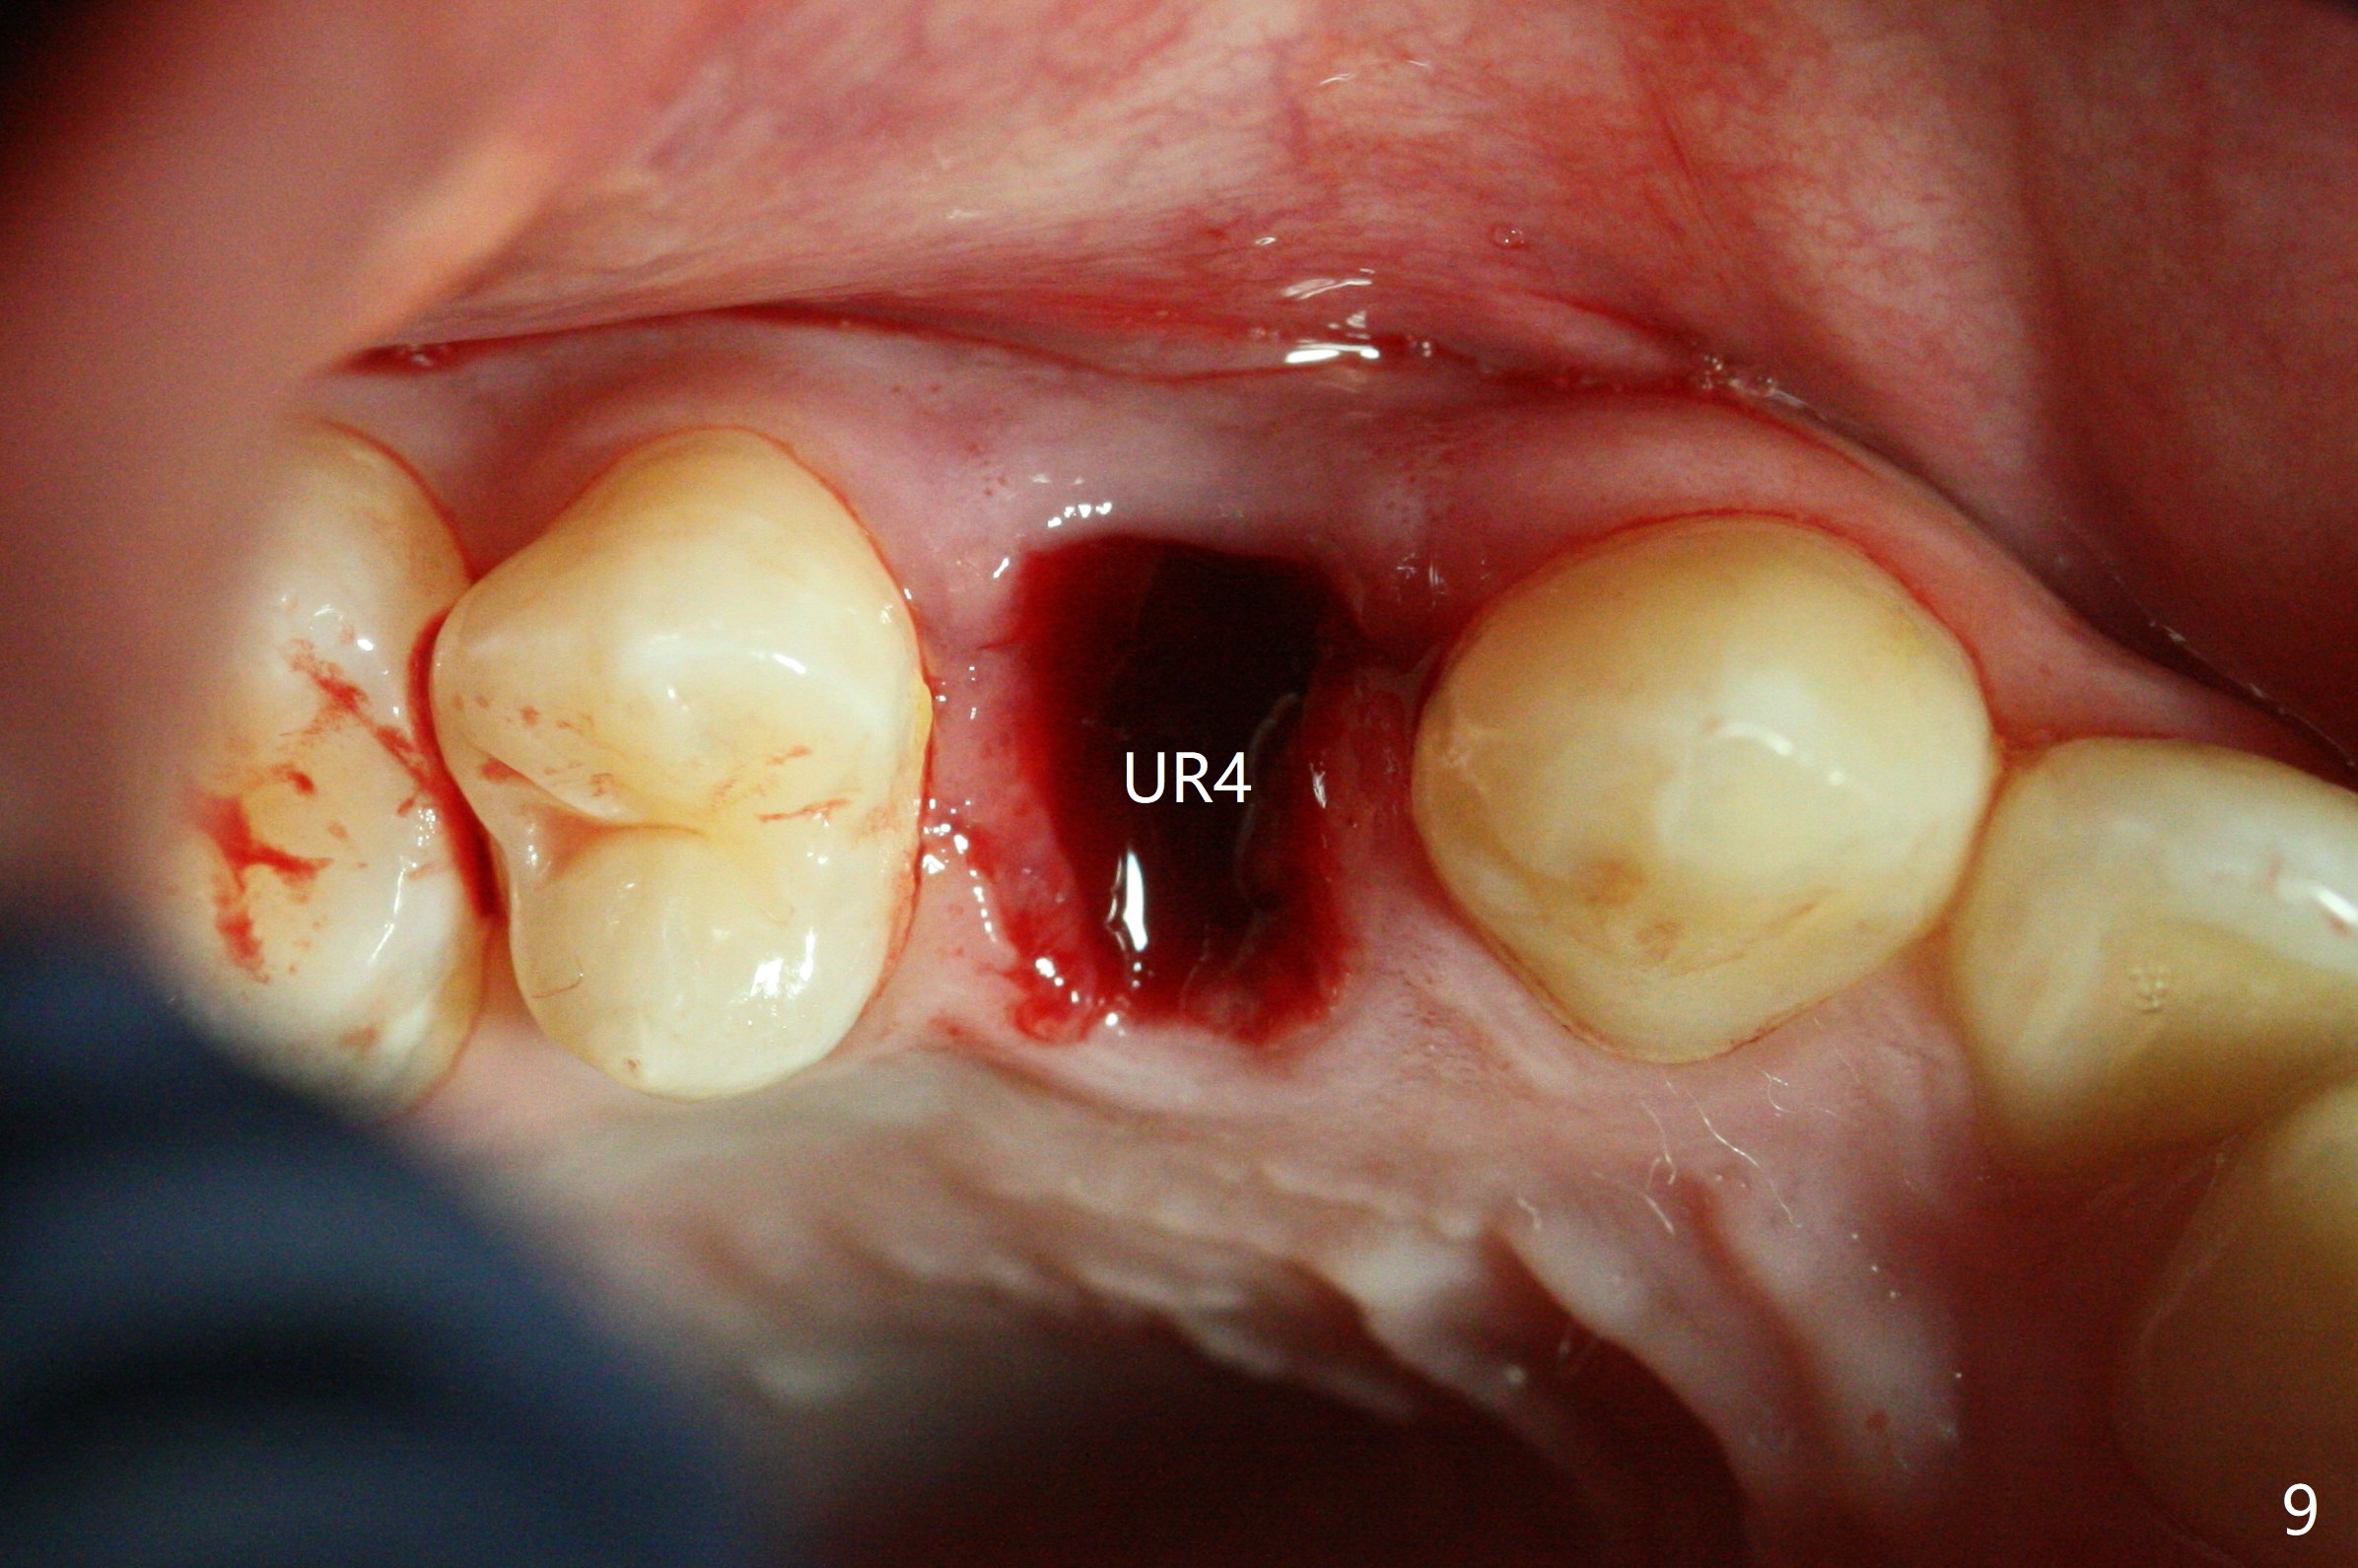

In fact, extraction of LR3 is easier than the other three, because of its labial socket (Fig.10 * (loss of the labial plate), as compared to Fig.9).  Nevertheless, the root of LR3 is the longest (Fig.11).